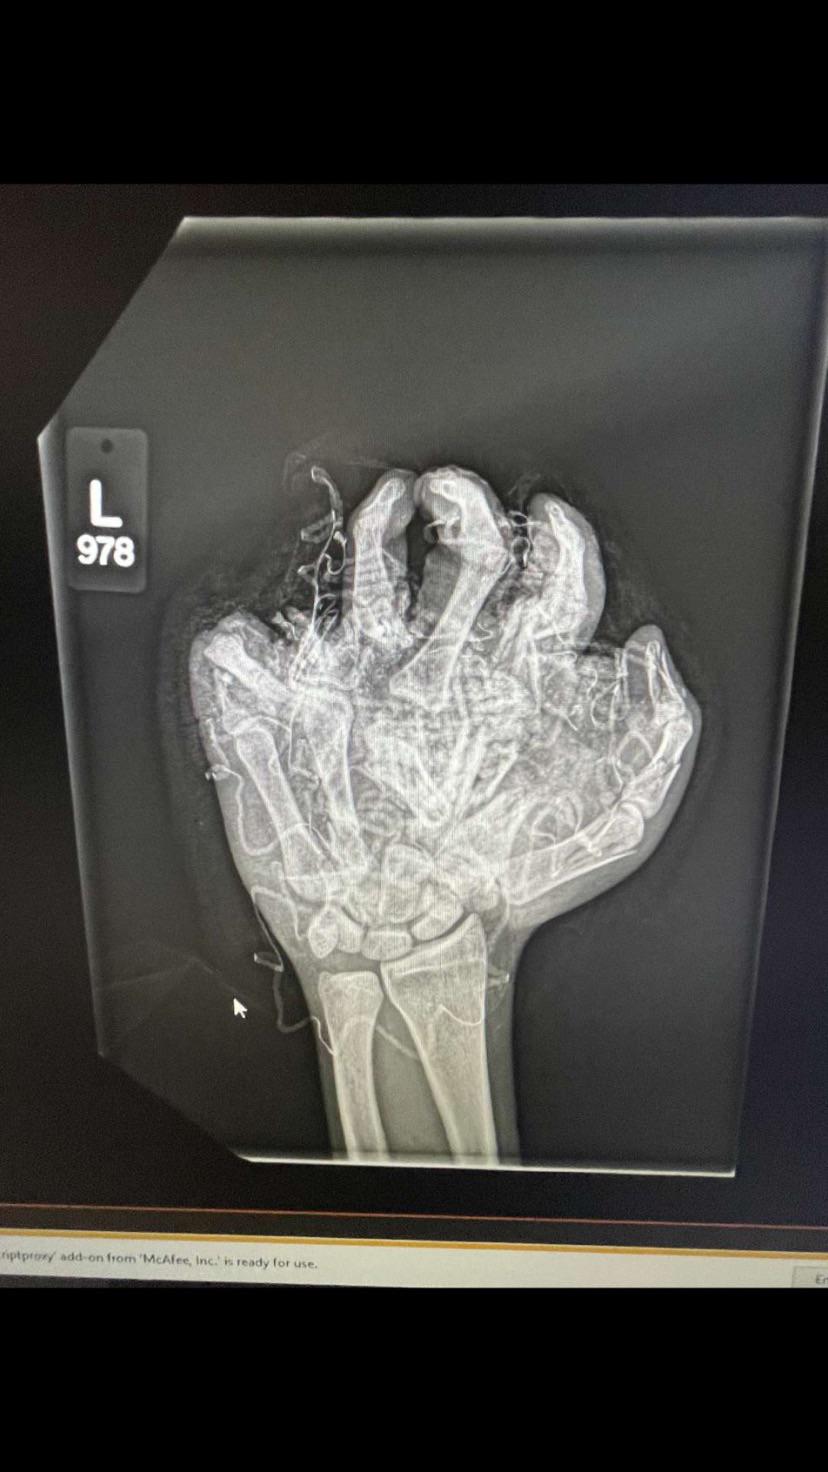

Increased bone density

Image Source: Reddit

Weightlifting can help improve your overall bone density, and reduce the risk of certain conditions e.g. osteoporosis. Your bone density is increased via weightlifting, because it helps strengthen your joints, as well as the connective tissue surrounding your bones.Advertisement